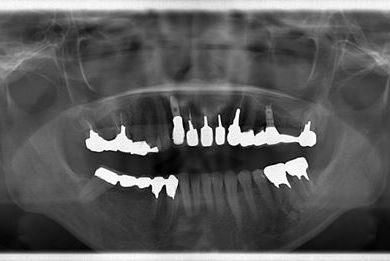

| 性別/年齢 | 女性 / 44歳 | ||||||||||||||||||||||||||||||||

| 主訴 | 上のさし歯がグラグラする。インプラントにした方が良いのか、相談したい。 | ||||||||||||||||||||||||||||||||

| 治療方針 | 抜歯と同時にインプラントを埋入し、治療期間を短縮する。 | ||||||||||||||||||||||||||||||||

| 治療内容 | インプラント2本(抜歯即日スピードインプラント)、メタルボンドセラミック2本 | ||||||||||||||||||||||||||||||||